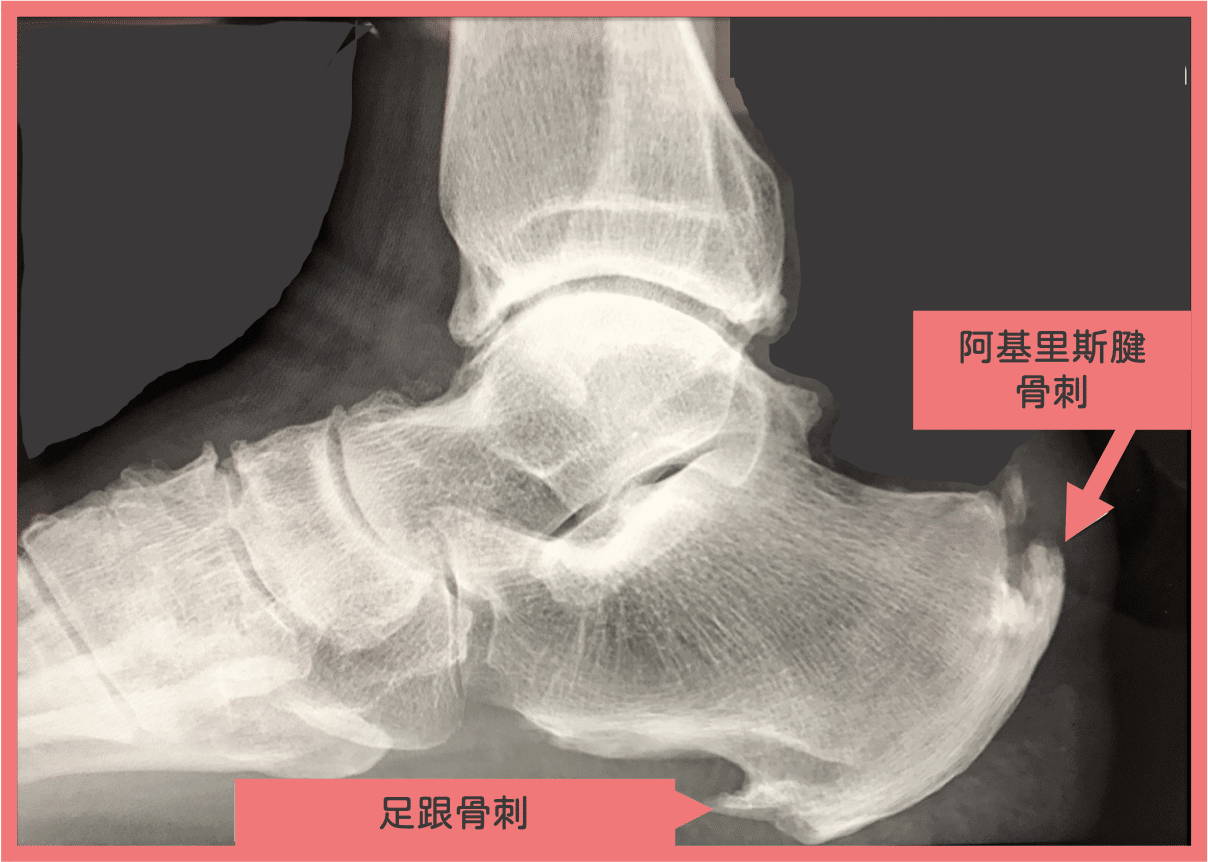

足跟長骨刺,就是足底筋膜炎嗎?

坊間常常會聽說,阿你足底長一根骨刺啦!所以那是足底筋膜炎!!

不只足跟會長骨刺,另一邊的阿基里司腱也會長骨刺。

足底會長骨刺,是因為足底筋膜長期的拉扯,或是小腿後面肌肉太緊的長期拉扯,

讓骨頭感受到壓力過大的訊號,所以長出骨刺。

而這個足跟骨刺 通常跟你的足底疼痛沒什麼直接關連,所以千萬不要開刀去切掉它

有部分足底筋膜炎的人的確有足跟骨刺,但是這是可以治療的。

只要接受 震波治療 或是 增生治療導引注射,足底痛就會好了。

有人問:那足跟骨刺還會在嗎?

還會在,但你會不疼痛,所以和平共處就好了。

*ps:有足跟骨刺的人 通常足底跟小腿都很緊繃,或是呈現 高足弓。

因此可以考慮 穿矯正鞋墊 分散腳底壓力